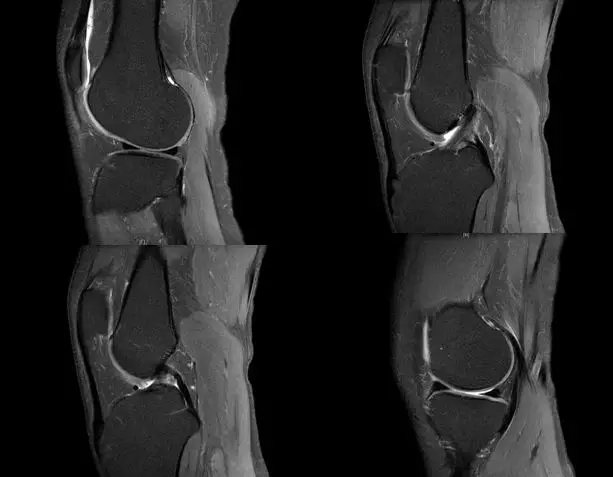

关节扭伤常常导致膝关节相关韧带结构的损伤,如何及时发现这些损伤并进行相关的治疗,是我们临床医师常常面临的问题,除了相关病史、临床体征之外,磁共振扫描也是重要的诊断依据

膝关节的解剖结构

正常的膝关节

韧带结构:形态,张力,质地,连续性

半月板:完整性,形态,质地